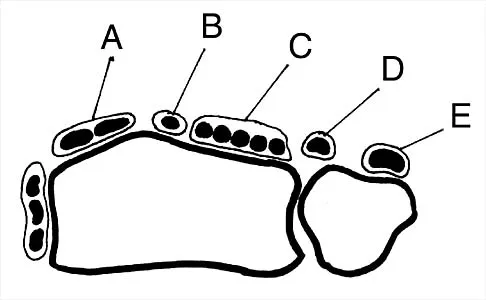

Figure 30 shows an axial cross section of extensor tendon anatomy in zone 7 of the wrist. What letter best depicts the location of the posterior interosseous nerve?

Explanation